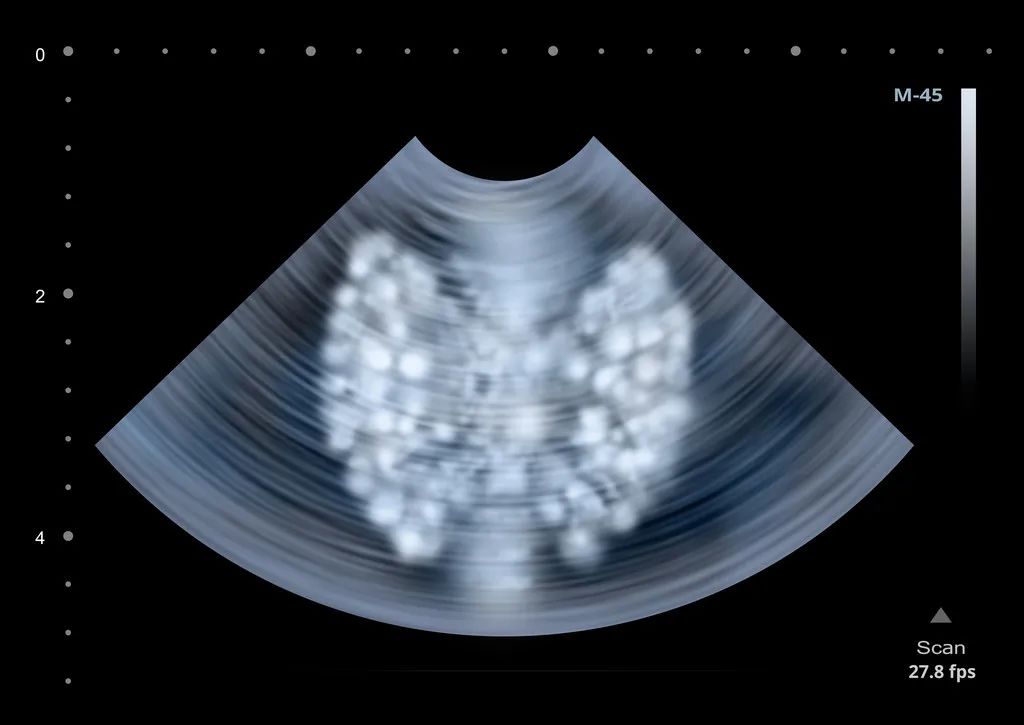

图文部分主要包括两个部分,分别是超声图像及超声描述。由于每个医院的超声报告系统大同小异,在存储的大量超声图片中选取1-2张图片,具有阳性诊断意义的图片作为代表。

超声描述部分就是对患者所检查的脏器大小形态进行基本检测并测值,并对脏器的整体及或占位性病变进行超声描述。在描述中会涉及到专业的名词,例如:无回声,常常代表液体(尿液,血液,积水,胆汁等);强回声,常常代表钙化,结石,骨骼,气体等;等回声,偏强回声,弱回声,偏低回声等等常常代表是实性组织,可以为脏器回声,或是占位性病变。在测量病灶的时候,对于报告中的数值,可能大家会发现有时数值会不一样。由于每一次切面略有不同,导致测量值略有不同。